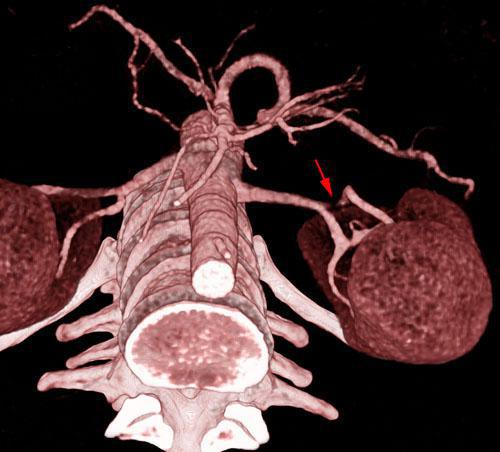

Estenosis por displasia fibromuscular de arterias renales